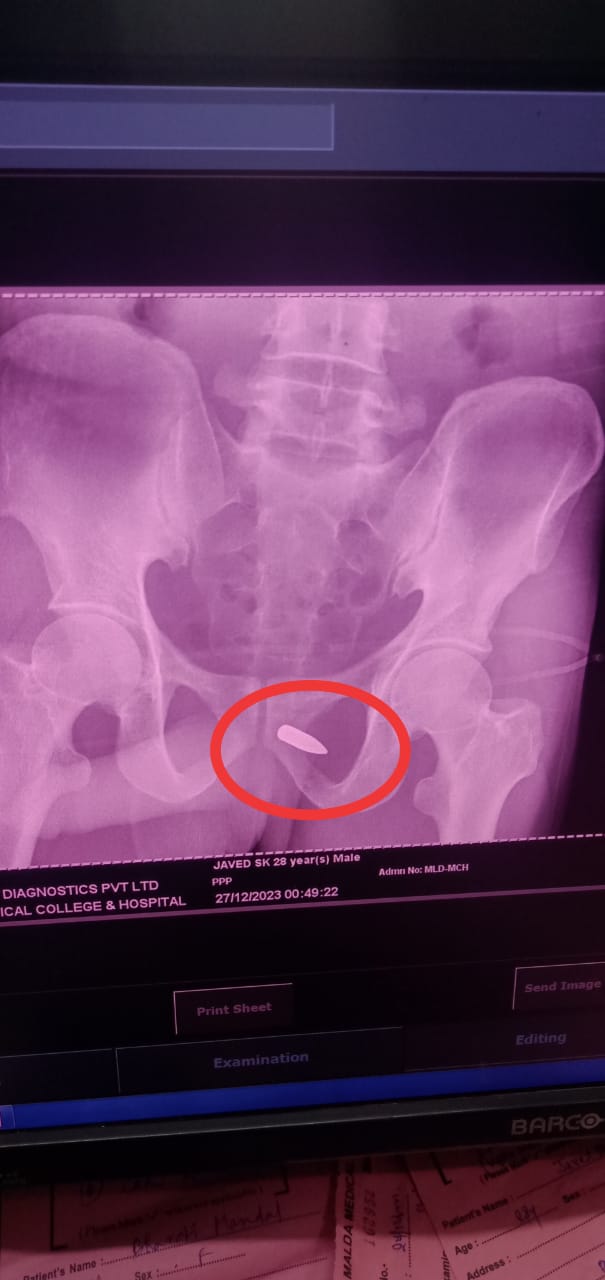

মালদা:- —————-–জালসা শুনে বাড়ি ফেরার পথে গুলিবিদ্ধ এক যুবক। মালদার কালিয়াচক থানার শাহাবাজপুর গ্রাম পঞ্চায়েতের বামুনটোলা এলাকার ঘটনা। গুলিবিদ্ধ যুবক মালদা মেডিকেল কলেজ হাসপাতালে চিকিৎসাধীন। জানা গেছে, গুলিবিদ্ধ যুবকের নাম জাবেদ শেখ (২৭), বাড়ি সংশ্লিষ্ট এলাকাতেই। পরিবার সূত্রে জানা যায় গতকাল রাত্রে বাড়ি থেকে কিছু দূরে জলসা শুনে বাড়ি ফিরছিল ওই যুবক। বাড়ি ফেরার পথে […]